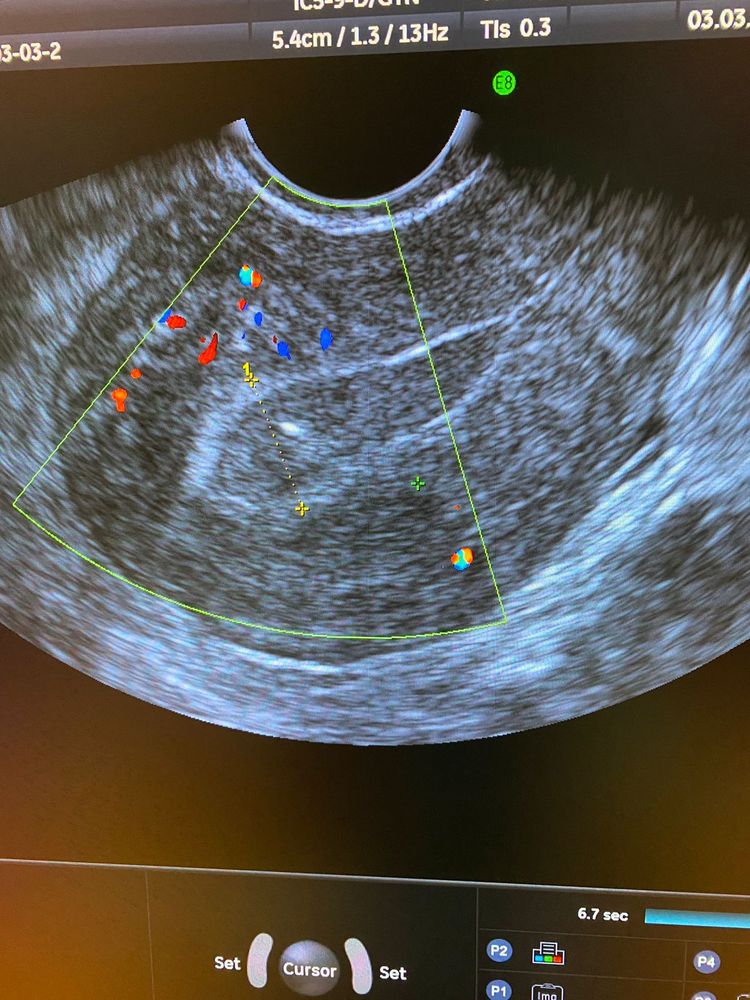

Была на узи 3 марта у своего врача. Картина такая

На отмене Утрика месячные так и не пошли( моя врач рекомендовала поехать в клинику и делать рдв, созвонилась с еще одним врачом, она подруга моей свекрови вместе учились в школе и в мединституте. Она посмотрела последние узи и тоже сказала про рдв и гистеру. Записалась на пятницу. Уже надоели все эти процедуры и манипуляции. Снова нужно оставить детей, снова наркоз, снова приём антибиотиков. Но ничего не поделаешь , надо, значит надо!